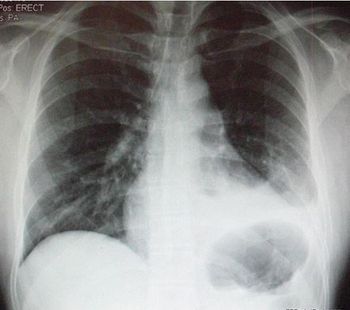

Worsening respiratory symptoms and fatigue of 6 months’ duration brought a 44-year-old woman in for evaluation. Diagnosed with asthma 2 years earlier, she was compliant with, but unresponsive to treatment. Your impressions?

The symptoms have worsened over a 2-month period. Past medical history is unremarkable. Here, review the ED chest x-ray film and ECG. Do you see any clues to a diagnosis?